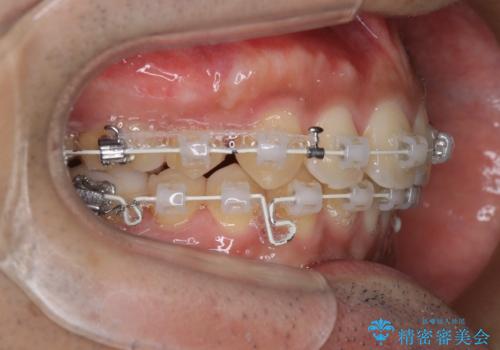

- 矯正装置

- 審美装置

- 歯並びの凸凹を主訴に来院されました。

スペースが必要なため、抜歯を行なって治療を行いました。

奥歯の捻れが強く治療期間がかかりましたが、綺麗な仕上がりに満足していただきました。

最初はインビザラインを治療していた経緯がありますが、使用時間が確保できずワイヤー矯正へ移行しております。